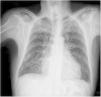

Chest radiography may be useful for assessing the disease in more advanced stages (Figure 1). Cardiomegaly with enlargement of the right and left heart chambers may be observed. However, pulmonary congestion is usually mild or non-existent.50

The Rassi score (Table 2) is used to stratify mortality risk in patients in the chronic phase and with cardiac involvement.99 The variables assessed in the score are gender, low QRS voltage on ECG, nonsustained ventricular tachycardia, global or segmental left ventricular wall motion abnormalities, cardiomegaly on chest X-ray and heart failure (NYHA class III or IV). The score estimates 10-year mortality risk, classifying patients as high risk (12-20 points), intermediate risk (7-11 points) or low risk (0-6 points). In the development and validation cohorts on which the score was based, the 10-year mortality rates for high, intermediate and low risk patients were 84-85%, 37-44% and 9-10%, respectively.99 The presence of nonsustained ventricular tachycardia is associated with a 2.15-fold increased risk of mortality, and the combination of this arrhythmia with left ventricular systolic dysfunction is associated with a 15.1-fold increased risk for subsequent death.100